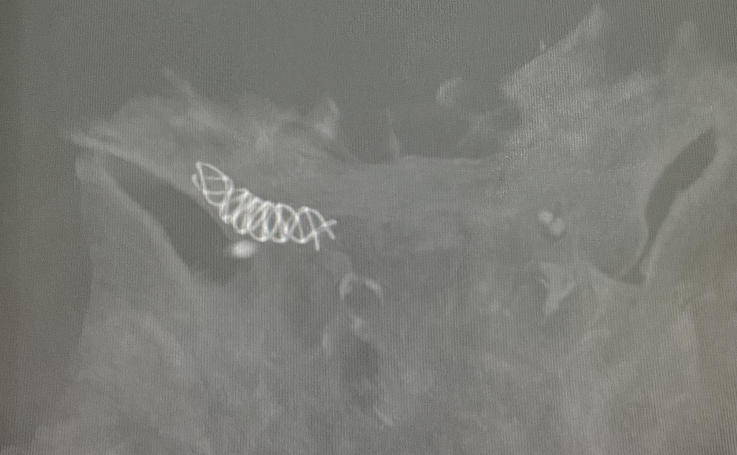

调整畅医达(Choydar)FD(2.5×20mm)至合适位置,瘤体内填入少量弹簧圈后支架半释放。

畅医达(Choydar)血流导向装置完全释放。